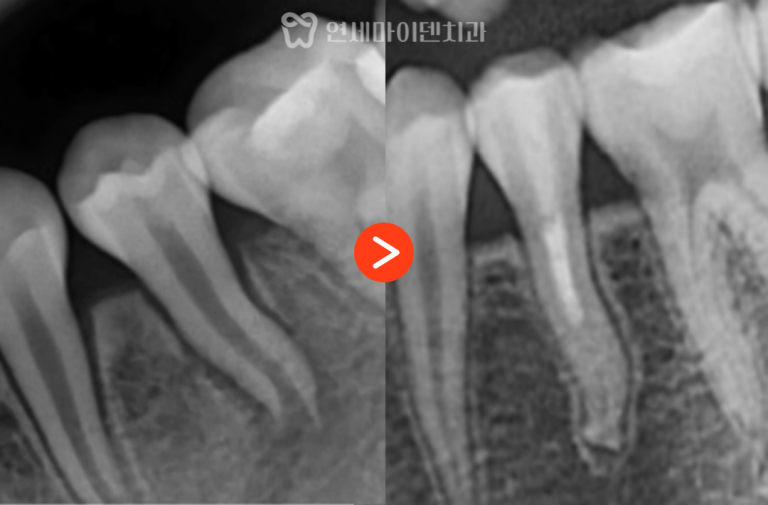

하지만 이 케이스에서는

치아 뿌리가 갈라지는 부위인

분지부까지 뼈가 녹아 있는 상태였습니다.

분지부 뼈가 손상되었다는 것은

치아를 지지하는 구조 자체가

무너졌다는 의미입니다.

여기에 더해

치아의 흔들림도 심하게 동반되어 있었고,

장기적으로 안정적인 유지가 어렵다고 판단되어

발치를 선택할 수밖에 없었습니다.